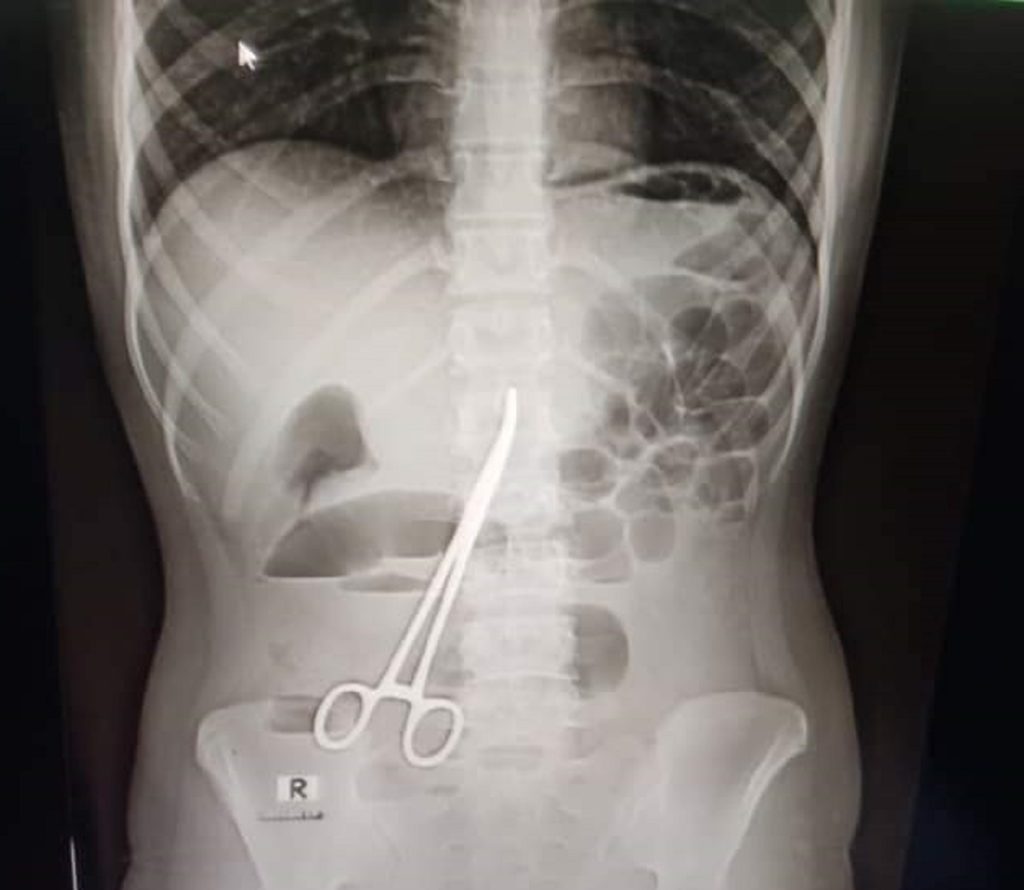

ফরিদপুর বঙ্গবন্ধু শেখ মুজিব মেডিকেল কলেজ হাসপাতালে এক তরুণীর অপারেশনের পর পেটের ভেতর কাঁচি রেখে সেলাই করে দেয়ার অভিযোগ উঠেছে। অপারেশনটি করা হয়েছিল গত বছরের মার্চে। সম্প্রতি মুকসুদপুরের এক হাসপাতালে এক্সরে করা হলে বিষয়টি ধরা পড়ে।

এরপর মনিরা অন্তঃস্বত্ত্বা হওয়ার পর বাচ্চা নষ্ট হলে তাকে বাবার বাড়িতে পাঠিয়ে দেন স্বামী। এরপরেও বিভিন্ন গ্রাম্য চিকিৎসা করানো হয়। কিন্তু তার পেট ব্যথা কমেনি। গত দু’দিন আগে পেটে অসহনীয় ব্যথা উঠলে তাকে মুকসুদপুরের একটি বেসরকারি ক্লিনিকে চিকিৎসার জন্য আনা হয়। ওই ক্লিনিকে এক্সরের মাধ্যমে চিকিৎসকরা দেখতে পান, মনিরার পেটের মধ্যে একটি ঝকঝকে কাঁচি আছে।

এ বিষয়ে মুকসুদপুর স্বাস্থ্য কমপ্লেক্সের কয়েকজন চিকিৎসক জানান, আমাদের সন্দেহ হলে তাকে একটি এক্সরে করতে বলি। পরে এক্সরে রিপোর্ট আসার পর কাঁচি দেখতে পাওয়া যায়। কয়েকজন চিকিৎসক বলছেন, গত বছরের ৩ মার্চ একটি অপারেশনের সময় ভুলে তার পেটের ভেতরে এ কাঁচিটি রেখে দেয়া হয়েছিল।

চিকিৎসকরা বলেছেন, ওই কাঁচির হাতলে সামান্য মরচে পড়ে গেছে এবং ওই যুবতীর পেটের ভেতরের অঙ্গ-প্রত্যঙ্গের সাথে জড়িয়ে গেছে এটি। দ্রুত অপারেশন করে কাঁচিটি বের করা না হলে রোগীর অবস্থা আরও খারাপ হতে পারে বলে জানান তারা।